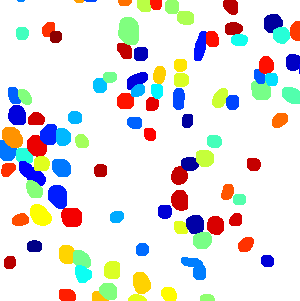

As an essential part of digital pathology, histopathology image analysis is playing increasingly important role in cancer diagnosis, which can provide direct and reliable evidence to diagnose the grade and type of cancer. This paper deals with nuclei segmentation, an important step in histopathological image analysis. The purpose of nuclei semgentation is not only counting the number of nuclei but also obtaining the detailed information of each nucleus. So unlike nuclei detection, here the outputs are the contour of each nucleus instead of only the position of their central points. Hence we can exactly extract each nucleus from the image and make it available for further analysis. For example, the features of the individual nucleus and the distribution of nuclei clusters can be used to grade and classify status of breast cancers [3, 4]. Because of appearance variation such as color, shape, and texture, nuclei segmentation from histopathological images could be very challenging, as illustrated in Fig.1, in which it is very challenging even for human to recognize and segment all nuclei within the images. Fig.1(a) and Fig.1(b) illustrate two histopathological images from different organs. Fig.1(c) and Fig.1(d) are two histopathological images from same organ but have different cancer grade.

Figure 6 shows how our method segments the nuclei step by step. The color variety is well controlled by the color normalization procedure. The prediction result shows clear nuclear areas and nucleus boundaries. In the final segmentation result and ground truth image, each nucleus is represented by a different color.